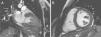

Case reportA 19-year-old woman presented palpitations and chest discomfort, unrelated to exertion and with no pleuritic characteristics, without reports of syncope, during the previous year. She had no relevant medical history and no known relevant family history of cardiac, renal, neurologic or genetic diseases; she was not under any medication and did not practice any sports. Her family physician performed a physical exam that was unremarkable (including blood pressure), except for an arrhythmia on cardiac auscultation. He requested an electrocardiogram (Figure 1A) which revealed sinus arrhythmia, biphasic T waves in leads DII, aVF and V3, and T-wave inversion in leads DIII and V4–V6. On the basis of this abnormal ECG clinical observation by a cardiologist was requested, in which the patient underwent more diagnostic exams. The echocardiogram revealed no significant abnormalities, except the presence of hypertrophic PMs (Figure 1B); LV mass was normal and maximum ventricular wall thickness was 11 mm at the interventricular septum in parasternal long-axis view. There were no significant valvular abnormalities. Despite the presence of prominent PMs, no significant intraventricular gradient or LV outflow tract obstruction was found on Doppler evaluation at rest. For further clarification and to assist with differential diagnosis, CMR imaging was performed. This exam showed a normal right ventricle and normal valve structures. The left ventricle had normal systolic function (60% ejection fraction), with a mass of 59 grams (35.5 g/m2), end-systolic volume of 42 ml and end-diastolic volume of 104 ml. Maximum ventricular wall thickness was 11.2 mm at the interventricular septum measured in end-diastole, 4-chamber view. Both PMs were also seen to be abnormally hypertrophic (Figures 2 and 3), occupying a large part of the LV cavity during systole (Figures 2A and 3A). The anterolateral PM had a maximum diameter of 12.5 mm and the posteromedial PM measured 15 mm on the horizontal axis (end-diastole, short-axis view; Figure 3B). Delayed hyperenhancement was not observed.

(A) 12-lead electrocardiogram showing the repolarization abnormalities described in the text. The voltage sum of the S wave in V1 and the R wave in V5 is 36 mm, but this patient was 19 years old, so the voltage criterion for left ventricular hypertrophy of ≥35 mm is not applicable; (B) echocardiographic image at the level of the papillary muscles (short-axis view at end-systole).